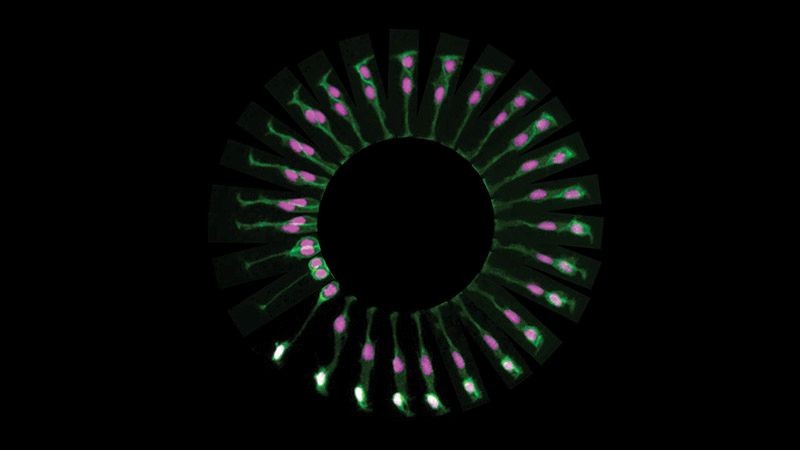

Paula Alexandre, que coordena um grupo de investigação no Institute of Child Health, da University College London, ganhou com uma imagem inédita, obtida com um microscópio confocal, da divisão celular no cérebro de um embrião de um peixe-zebra.

O trabalho da cientista Paula Alexandre incide na compreensão de como as células neuronais se formam normalmente e de como existem alterações quando ocorrem anomalias no cérebro.

O microscópio confocal que utilizou permitiu obter imagens de amostras vivas da sequência de uma divisão celular, neste caso de um ‘progenitor neuronal’, que dá origem a neurónios (células do sistema nervoso), e de células cerebrais.